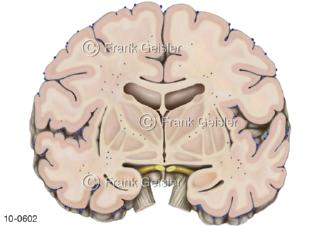

Bildergalerie Nervensystem

Bilder zum Nervensystem,dem Gehirn, Teil des zentralen Nervensystem, Zentralnervensystem ZNSmit Rückenmark, Abbildungen zum Nervengeflecht (Nervenplexus), die Verflechtungen von Nervenfasern, aus der Wirbelsäule hervortretende Nervenäst sowie Nervenzellen der Nerven